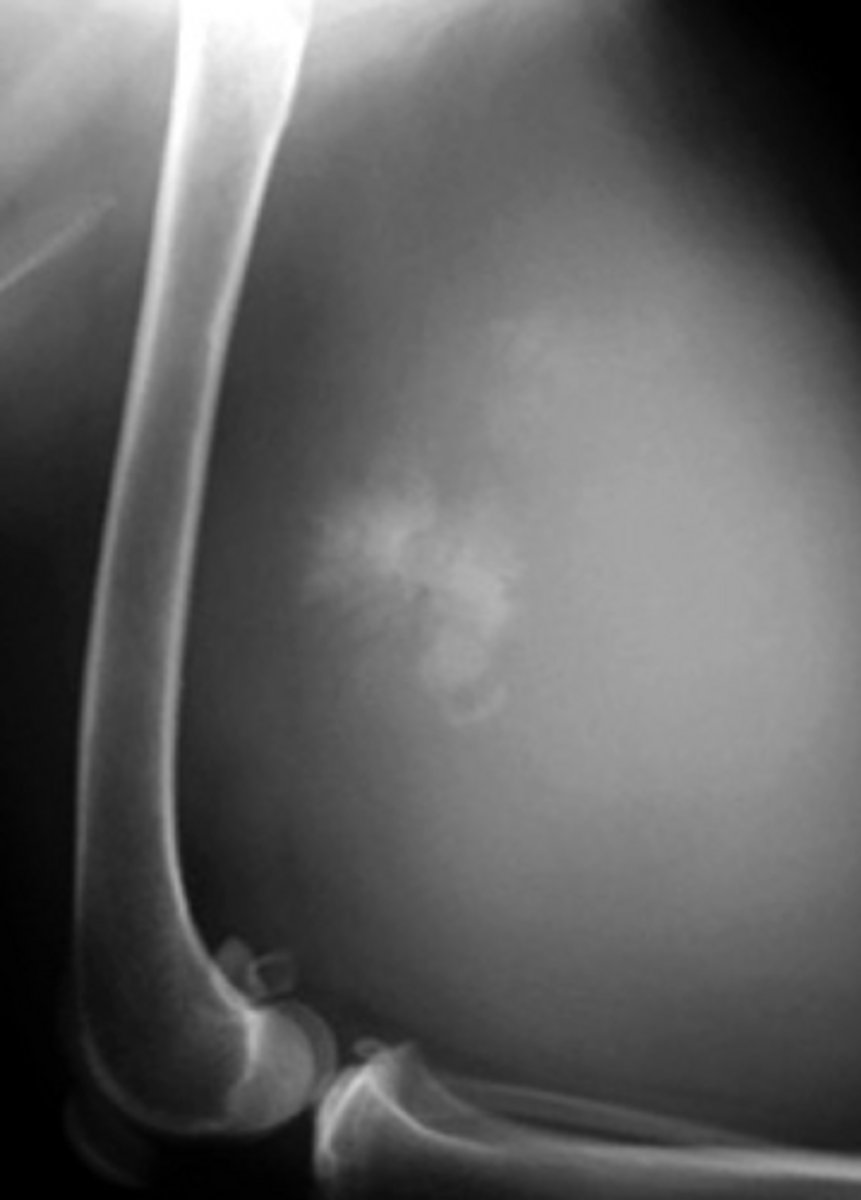

Identify the joint changes?

Non-erosive

Erosive or non erosive?